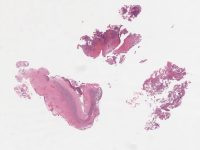

AANP2002-2.svs

72000 x 43994

@ 20X